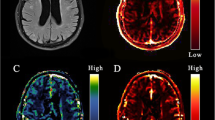

This was done on a voxel-level for visualization (Fig. 1) and on a ROI-level for evaluation of PS and \({v}_{p}\) against other variables (e.g., age, cognition, and 4D flow hemodynamics). In addition, PS and \({v}_{p}\) were averaged over basal ganglia, WM, cortical GM, and whole-brain (15 × ROIs) for evaluation against MoCA and 4D flow hemodynamics. The full \({C}_{tissue}\) and \({C}_{VIF}\) curves were used as input to the Patlak model for the main analyses. Since the contrast peak may not always be accurately estimated due to limited temporal resolution of the DCE scan, supplementary analyses were performed to assess the effect of including vs. excluding the contrast injection peak (Sup. Fig. 1). Further, as the RF pulse excitation profile may be non-uniform at the edges of the axial slab (Sup. Fig. 3), supplementary analyses between region-averaged PS values and MoCA score were performed after excluding the frontal and parietal cortex (Sup. Fig. 4).

T1 maps (seconds) at baseline, the permeability-surface area product (PS; min−1), and fractional plasma volume (\({v}_{p}\)) for an example participant. The T1 maps were obtained using the variable flip angle method, and PS and \({v}_{p}\) were obtained using Patlak analysis. Note that while the images are thresholded according to the color bars to aid visualization, no thresholding or exclusion based on extreme values was used for any of the results.